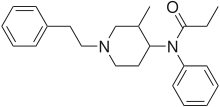

The pharmacodynamic response to an opioid depends upon the receptor to which it binds, its affinity for that receptor, and whether the opioid is an agonist or an antagonist. For example, the supraspinal analgesic properties of the opioid agonist morphine are mediated by activation of the μ1 receptor; respiratory depression and physical dependence by the μ2 receptor; and sedation and spinal analgesia by the κ receptor. Each group of opioid receptors elicits a distinct set of neurological responses, with the receptor subtypes (such as μ1 and μ2 for example) providing even more [measurably] specific responses. Unique to each opioid is its distinct binding affinity to the various classes of opioid receptors (e.g. the μ, κ, and δ opioid receptors are activated at different magnitudes according to the specific receptor binding affinities of the opioid). For example, the opiate alkaloid morphine exhibits high-affinity binding to the μ-opioid receptor, while ketazocine exhibits high affinity to ĸ receptors. It is this combinatorial mechanism that allows for such a wide class of opioids and molecular designs to exist, each with its own unique effect profile. Their individual molecular structure is also responsible for their different duration of action, whereby metabolic breakdown (such as N-dealkylation) is responsible for opioid metabolism.

Anilidopiperidines

Phenylpiperidines